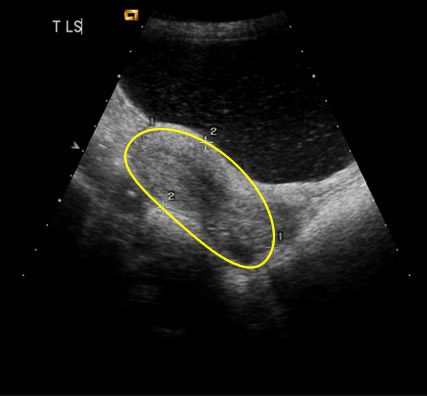

| Fig 2 The uterus is usually situated centrally in the pelvis behind the full bladder (bladder is highlighted) | Zoom |